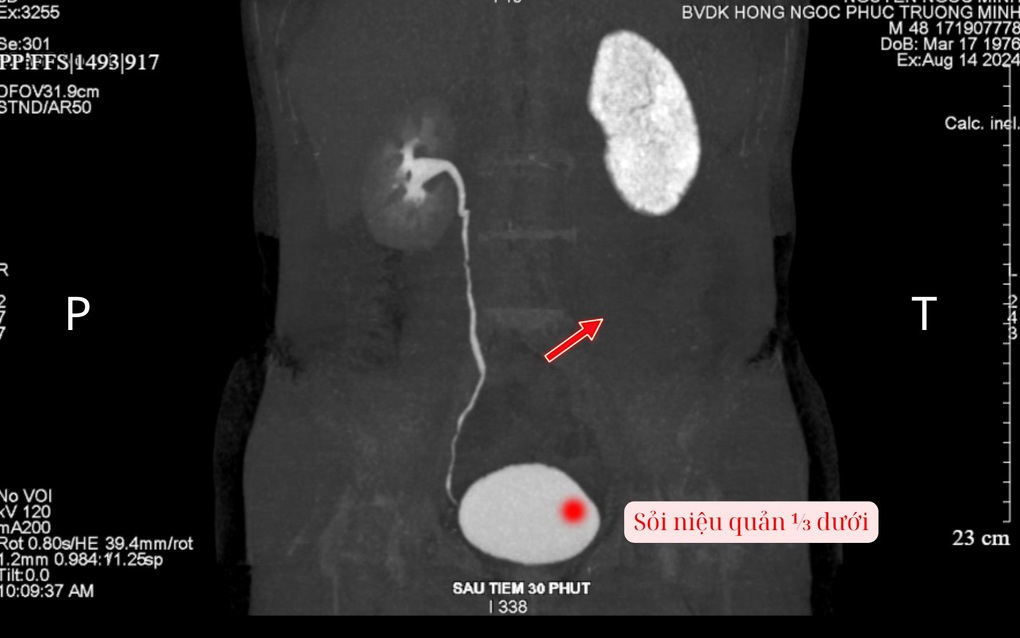

Trường hợp của bệnh nhân N.N.M (35 tuổi) là ví dụ điển hình cho thấy hiệu quả của việc can thiệp kịp thời trong "thời gian vàng". Anh M nhập viện trong tình trạng đau dữ dội vùng thắt lưng trái, kèm biểu hiện đau tức khi tiểu. Kết quả chụp CT cho thấy niệu quản bên trái hoàn toàn không ngấm thuốc cản quang, chứng tỏ đường tiểu đã bị viên sỏi làm tắc nghẽn hoàn toàn, thận trái đã mất chức năng tạm thời.

Niệu quản phải tắc nghẽn, không ngấm thuốc cản quang (Ảnh: BVCC).